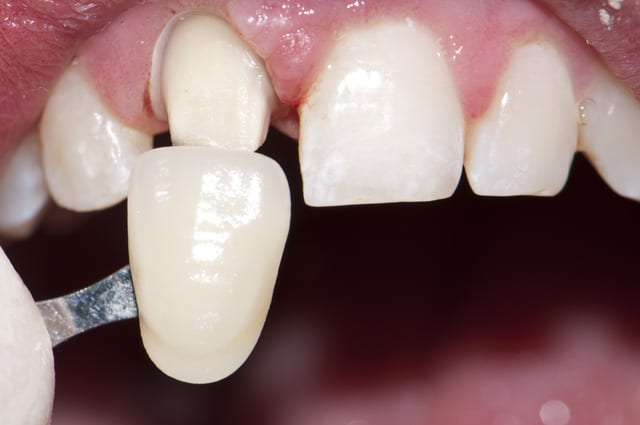

voila quelques traitements,modestes mais je suis encore jeune....